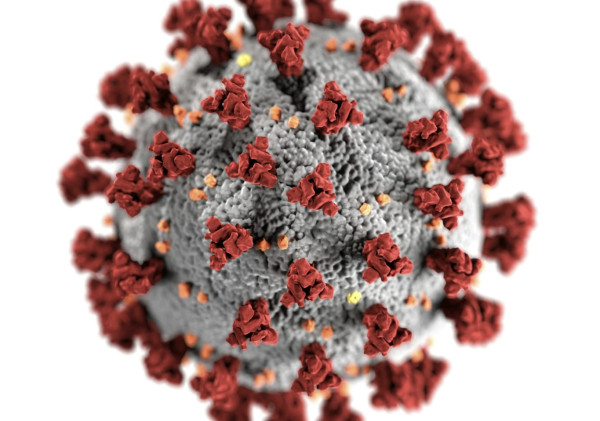

Varian Covid FLiRT Muncul sebagai Ancaman Baru? Apa Dampak Dan Langkah-langkah pencegahannya, Simak selengkapnya!

Minggu, 14 Juli 2024 | 20:55 WIB